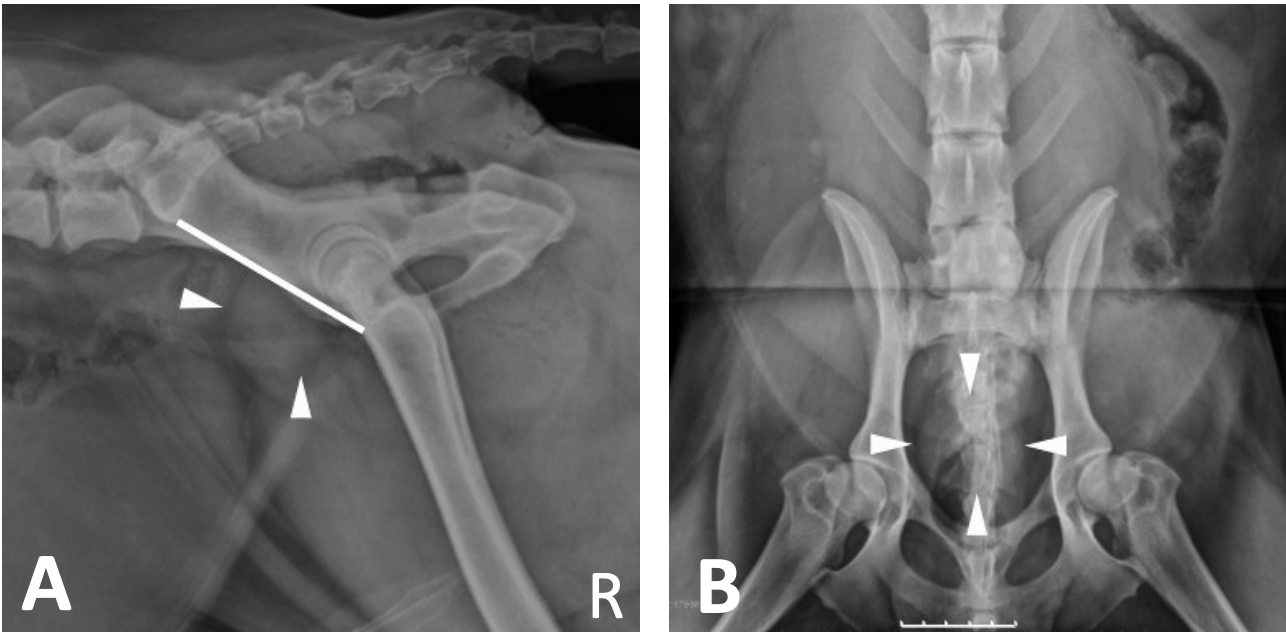

What is shown in these images?

A

normal prostate in an intact dog

-arrow heads indicate the prostate

-white line represents distance between sacral promontory and pubis